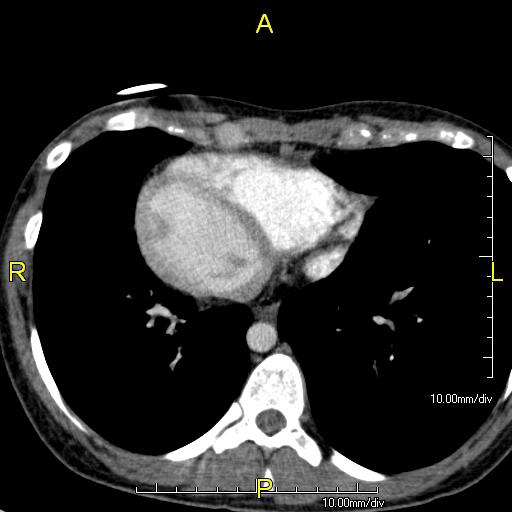

이 상태는 흉강과 복강 내의 모든 주요 장기에 영향을 미친다. 일반적으로 장기는 시상면을 기준으로 좌우가 바뀐다. 심장은 흉강의 오른쪽에, 위와 비장은 복부의 오른쪽에, 간과 담낭은 왼쪽에 위치한다. 심장의 정상적인 오른 심방은 왼쪽에, 왼 심방은 오른쪽에 위치한다. 폐의 구조도 바뀌어 왼쪽 폐는 세 개의 엽, 오른쪽 폐는 두 개의 엽을 가진다. 혈관, 신경, 림프관을 포함한 다른 내부 구조도 마찬가지로 좌우가 바뀐다.

심장이 흉강의 오른쪽에 있는 경우를 "우심증을 동반한 내장 역위증" 또는 "완전 내장 역위증"이라고 한다. 심장이 흉강의 왼쪽에 남아있는 매우 드문 경우(200만 명 중 1명 꼴)는 "좌심증을 동반한 내장 역위증" 또는 "불완전 내장 역위증"이라고 한다.

''내장 역위증''의 진단은 영상 기술, 예를 들어 X-레이, 초음파, CT 스캔, 자기 공명 영상 (MRI) 등을 사용하여 내릴 수 있다.[10]